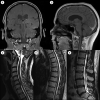

Ewing sarcoma (ES) is an aggressive, high-grade neuroectodermal neoplasm that frequently manifests in children and young adults. Although ES without osseous involvement most commonly involves paravertebral regions of the spine, it very rarely presents as a primary intracranial tumor. This report discusses a unique presentation of an adult extraosseous ES arising from the pineal region with extension into the third and fourth ventricles and multiple drop metastases to the spine. This case demonstrates the application of current chemotherapeutic and adjuvant management and offers insight into possible treatment modalities for metastasis in an atypical extraosseous ES involving the brain and spine.